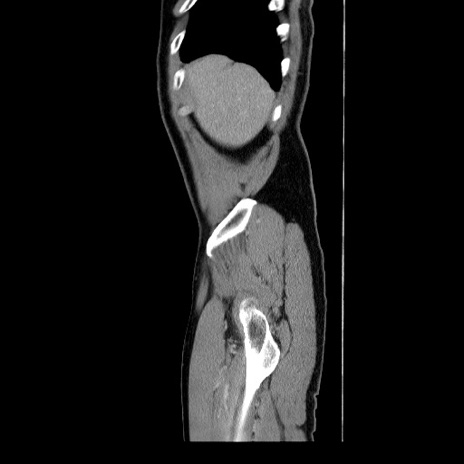

冠状断像

【症例】60歳代 男性

【主訴】右鼠径部膨隆

【現病歴】1年程前より右鼠径部膨隆あり。自己にて還納可能だったため放置していた。3時間前より右鼠径部の脱出を認め、還納困難となり受診。

【身体所見】右鼠径部に小児頭大の膨隆あり。弾性硬であり、用手還納は困難。左鼠径部にも膨隆を認める。脱出はなし。